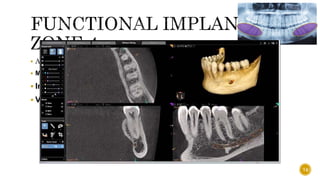

ZONE 1

 Also known as the “traumatic zone”

 1. BONE

 Part of the anterior maxilla is a protruding alveolar

process with thin labial and thick palatal cortical plates

covering and protecting upper front teeth.

 Evaluate the deficiency